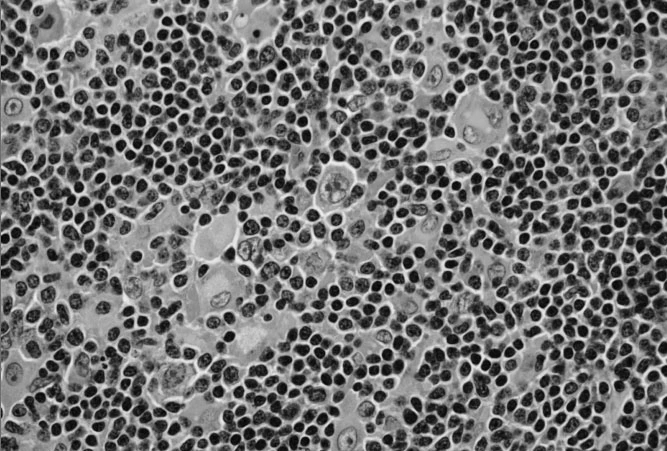

Lymphoma

Lymphoma is cancer that starts in lymphocytes (a type of white blood cell that is important in the immune system). As lymph tissue is found throughout the body, lymphoma can begin almost anywhere.